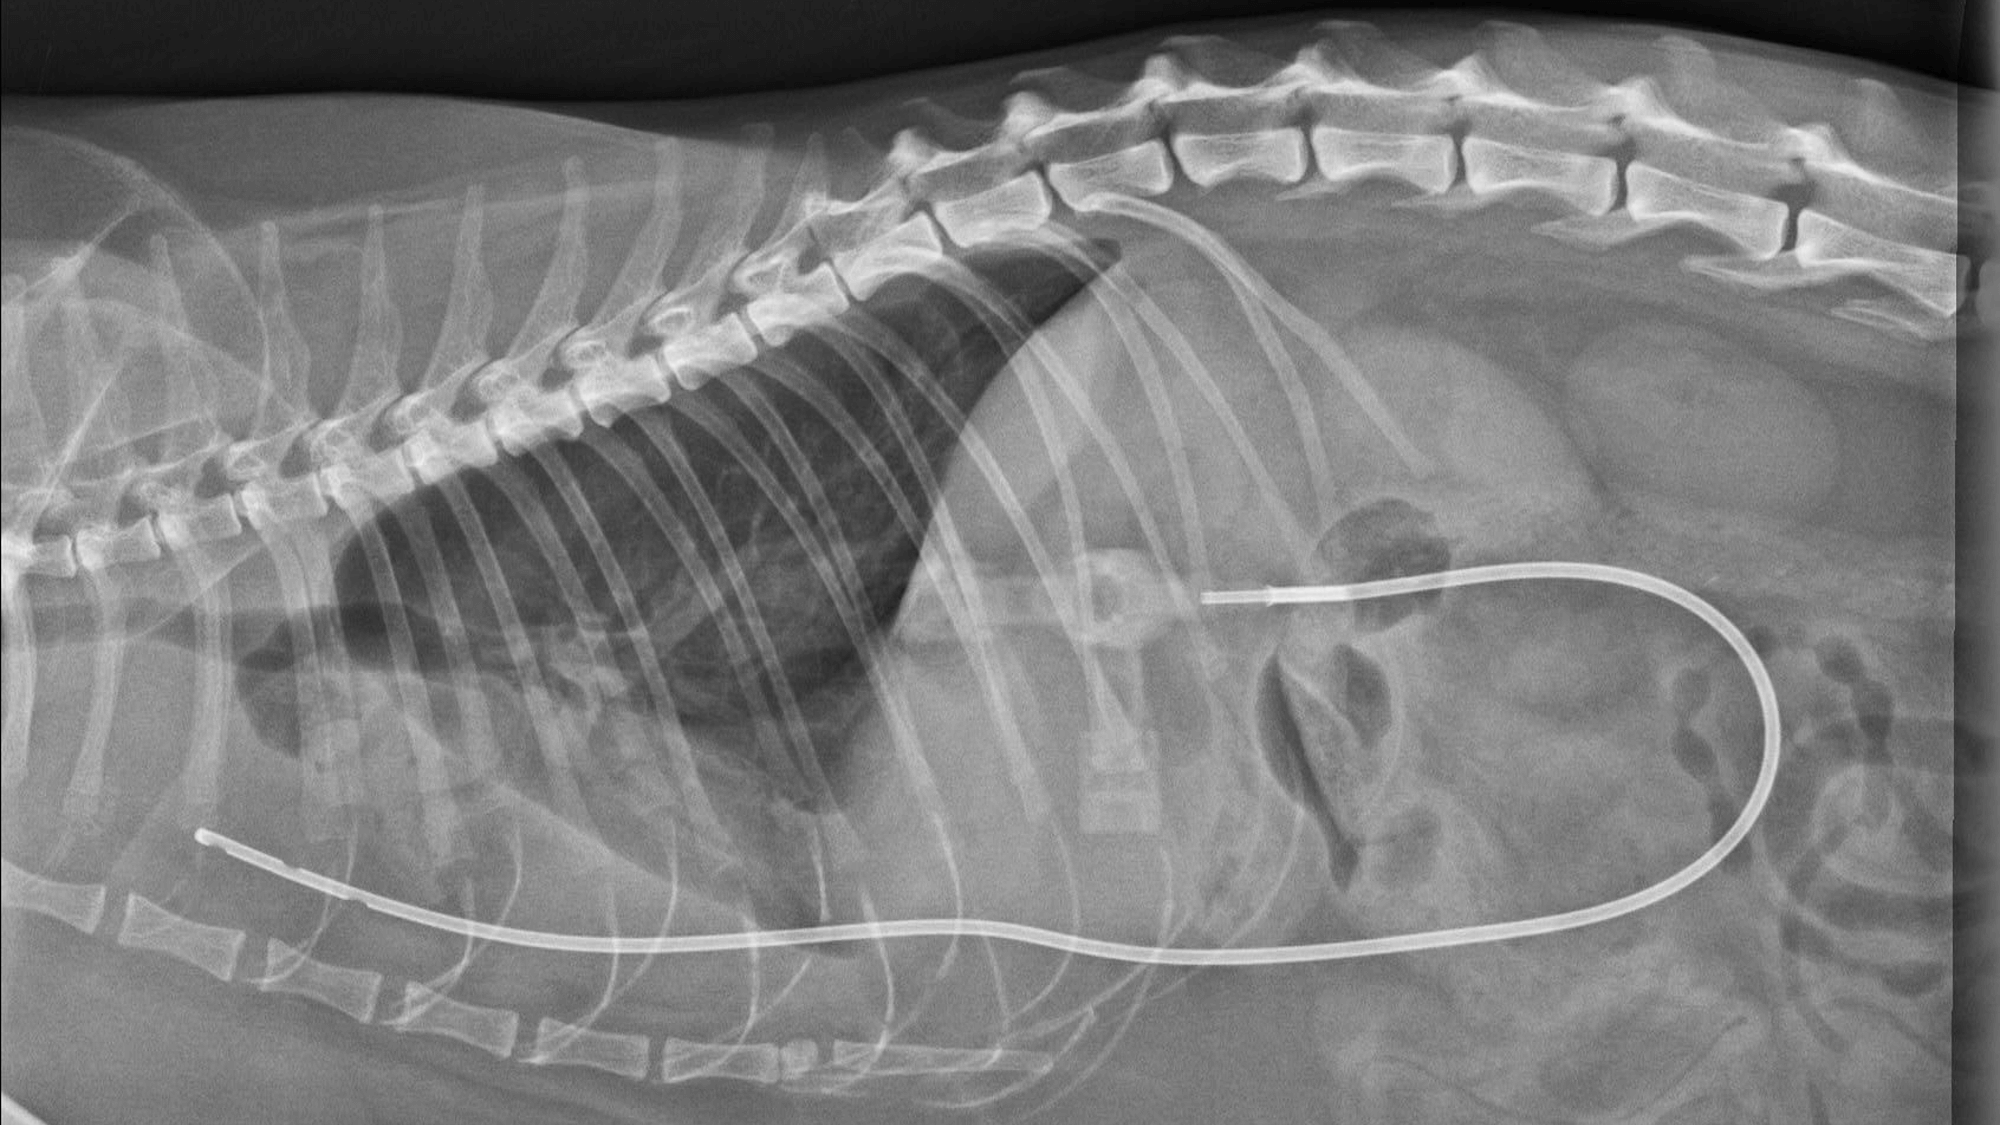

RTG: velké množství pleurální efúze (zvýšená opacita ventrálně, neohraničitelná srdeční silueta, odsunutí plicních laloků dorzálně)

RTG: hrudní drén zavedený do hrudní dutiny